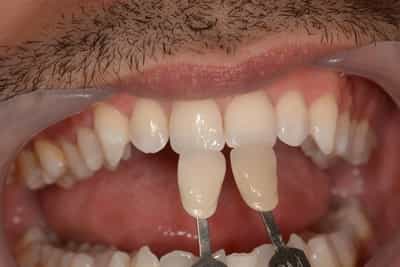

Eclaircissement Dentaire ou Blanchiment

L’éclaircissement dentaire est une technique consistant à rendre aux dents une couleur plus harmonieuse, plus en adéquation avec l’image que le patient veut donner de lui. Le blanc des yeux est une référence. A l’échelle du visage, la blancheur de la sclérotique de l’oeil (blanc des yeux) fait ressortir la couleur jaune des dents. Pour une meilleure harmonie, il faut aligner ces deux couleurs. Si les dents sont moins lumineuses, l’éclaircissement va améliorer l’apparence. Après éclaircissement, cette différence s’atténuera et donnera une harmonie du visage.

Souvent, il sera plus judicieux de réaliser un éclaircissement avant un travail prothétique, ou des composites antérieurs, car les techniques d’éclaircissements ne sont pas actives sur les céramiques ou les composites.